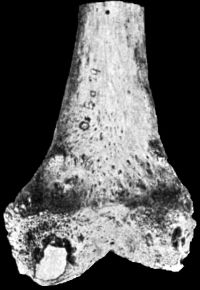

| 167. | Lower End of Humerus from case of Cubitus Varus | 309 |

| 120. | Upper End of Femur in advanced Arthritis Deformans of Hip | 226 |

| 121. | Femur in advanced Arthritis Deformans of Hip and Knee Joints | 227 |